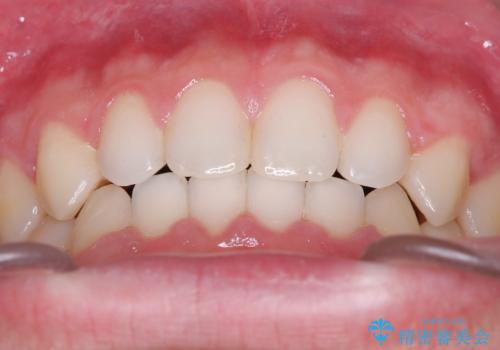

- 主訴:上の歯列の空隙を閉じたい

上顎前歯部に空隙が目立ちました。ワイヤー矯正、インビザライン(マウスピース矯正)どちらの方法でも適用症例と説明し、ワイヤー矯正治療(審美装置)を希望されました。

上顎歯列の空隙を閉じるのと一緒に、ディープバイト気味の被蓋も下顎前歯の圧下を行い改善しました。